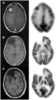

Minimally enhancing intracranial lesion

A traumatic brain injury (TBI), also known as an intracranial injury, is an injury to the brain caused by an external force. TBI can be classified based on severity (ranging from mild traumatic brain injury [mTBI/concussion] to severe traumatic brain injury), mechanism (closed or penetrating head injury), or other features (e.g., occurring in a specific location or over a widespread area). [Source: Wikipedia ]